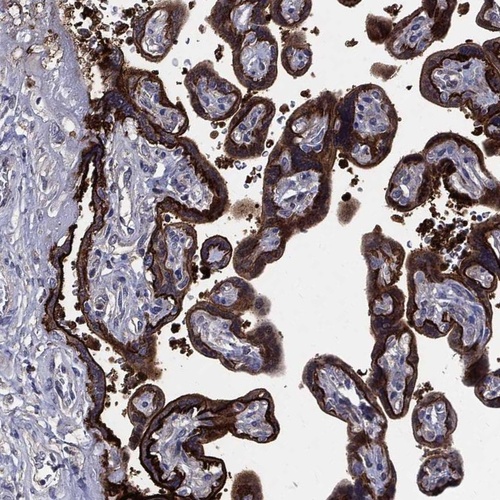

Immunohistochemical staining of human placenta shows strong positivity in trophoblastic cells.